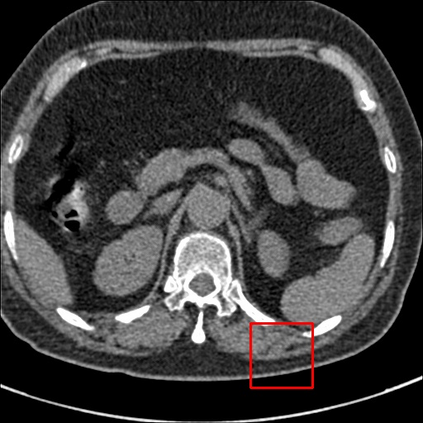

Low-Dose Computed Tomography (LDCT) technique, which reduces the radiation harm to human bodies, is now attracting increasing interest in the medical imaging field. As the image quality is degraded by low dose radiation, LDCT exams require specialized reconstruction methods or denoising algorithms. However, most of the recent effective methods overlook the inner-structure of the original projection data (sinogram) which limits their denoising ability. The inner-structure of the sinogram represents special characteristics of the data in the sinogram domain. By maintaining this structure while denoising, the noise can be obviously restrained. Therefore, we propose an LDCT denoising network namely Sinogram Inner-Structure Transformer (SIST) to reduce the noise by utilizing the inner-structure in the sinogram domain. Specifically, we study the CT imaging mechanism and statistical characteristics of sinogram to design the sinogram inner-structure loss including the global and local inner-structure for restoring high-quality CT images. Besides, we propose a sinogram transformer module to better extract sinogram features. The transformer architecture using a self-attention mechanism can exploit interrelations between projections of different view angles, which achieves an outstanding performance in sinogram denoising. Furthermore, in order to improve the performance in the image domain, we propose the image reconstruction module to complementarily denoise both in the sinogram and image domain.